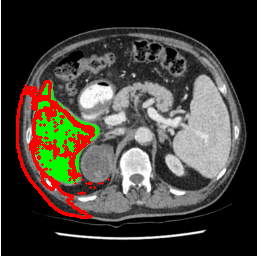

Our primary findings comparing the proposed model to baseline fully-supervised models when segmenting the liver from the LiTS dataset are reported in Table 1. The reported results demonstrate that our SAM-Mix model consistently achieves higher Dice scores compared to the fully supervised baselines as well as the two-stage SAM-PP method. Against U-Net, the best-performing fully supervised method, the SAM-Mix variant trained on 50 segmentation labeled slices (SAM-Mix-50), achieves a Dice score improvement of 5.9%. In terms of Hausdorff distance, while the fully-supervised baselines do slightly outperform SAM-Mix-5 and SAM-Mix-100, SAM-Mix-50 does achieve a lower Hausdorff distance by 22.38%. Qualitative evaluation as shown in Figs. 3 further affirms the superiority of SAM-Mix over baseline and existing fully-supervised methods as well as the two-stage SAM-PP variants. Furthermore, the boxplot visualization in Fig. 2 showcases consistently improved performance by SAM-Mix outperforming all the fully supervised and semi-supervised methods.

To test the generalizability of SAM-Mix, we validate it on a cross-domain dataset (TotalSegmentator). As reported in Table 2, the segmentation performance of SAM-Mix on the cross-domain task is as promising as the in-domain results. Despite the data shifts, from LiTS to TotalSegmentator, SAM-Mix outperforms all of the baseline models in terms of generalizability, by significant margins. SAM-Mix-50 achieves a Dice score improvement of 25.4%, and a lower Hausdorff distance by 62.26% compared to the best-performing full-supervised U-Net model. These results further validate the few-shot capabilities and establish our SAM-Mix as a well-generalized tool for medical image segmentation.